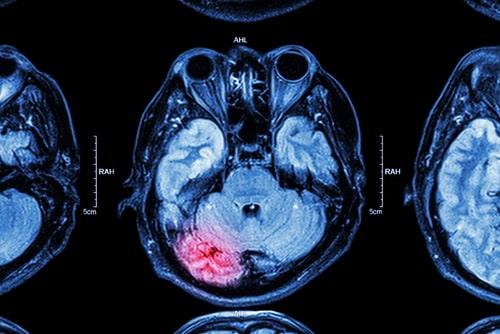

Traumatic brain injuries (TBI) are one of the most severe forms of personal injury that can befall a person. Tragically, these types of injuries can profoundly impact the lives of those suffering from them and their family. As a result, it is essential to understand the effects of such injuries and the potential legal ramifications of suffering a severe injury such as a TBI.

A traumatic brain injury occurs when an external force causes damage to the brain. This can happen for many reasons, including car accidents, sports injuries, falls, or even physical assault. Today, we will discuss the wide-ranging symptoms and effects of such injuries and the legal remedies available for someone who suffers this type of injury. If you have suffered a TBI and are wondering what legal options you may have, contact a personal injury attorney who will ensure that your rights remain protected and respected and that a positive case outcome can be pursued in your favor.

The extent to which someone is injured can play a significant role in the symptoms they experience. For example, if someone experiences a mild TBI, symptoms may include headaches, confusion, dizziness, and fatigue. However, more severe TBIs can lead to loss of consciousness, seizures, paralysis, and even death. TBI can have long-lasting and life-altering effects. In severe cases, individuals may experience various physical, cognitive, and emotional changes. These can include difficulty with balance and coordination, speech and language difficulties, memory and concentration problems, and changes in mood and behavior.